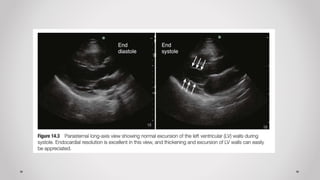

a) Mặt cắt dọc cạnh ức (Parasternal long axis plane)

2. Đánh giá chức năng thất Trái

Trường hợp không có máy siêu âm tim chuyên biệt  có thể đánh giá bằng “mắt” các

tiêu chí sau của thất Trái:

a) Kích thước: buồng tim (bình thường/giãn), cơ tim (bình thường, dày, mỏng)

b) Hình dạng: hạt đậu, trái chuối

c) Chức năng co bóp: bình thường, tăng, giảm

d) Vận động vùng: bình thường, nghịch thường, giảm động, vô động